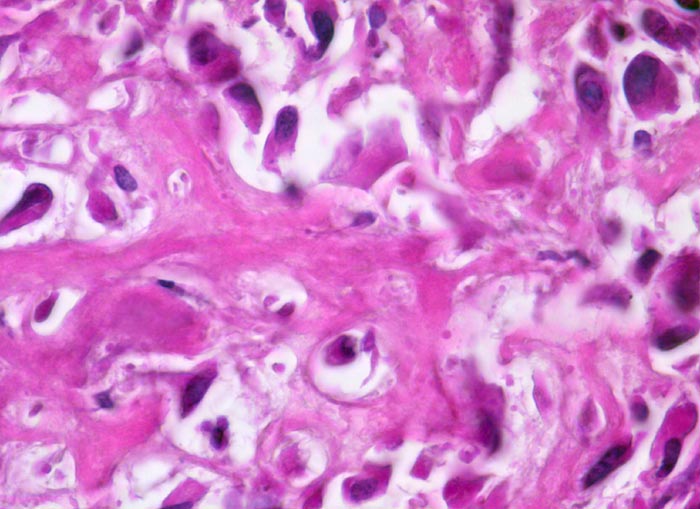

Osteosarkom

Knochen, Femur

Netz aus schmalem, verzweigtem, teils verkalktem, neugebildetem Tumorosteoid, das direkt von stark polymorphen mesenchymalen Tumorzellen mit hyperchromatischen Kernen gebildet wird. Die Zytomorphologie ist nach Entkalkung nur eingeschränkt beurteilbar.

Der Nachweis von Osteoid, das von atypischen Zellen gebildet wird, ist das wichtigste Kriterium für die Diagnose eines Osteosarkoms. Osteosarkome können aber auch auf weiten Strecken ausschliesslich chondroide oder fibröse Matrix bilden und dann ein Fibrosarkom, Chondrosarkom oder ein malignes fibröses Histiozytom imitieren.

Histologie

630